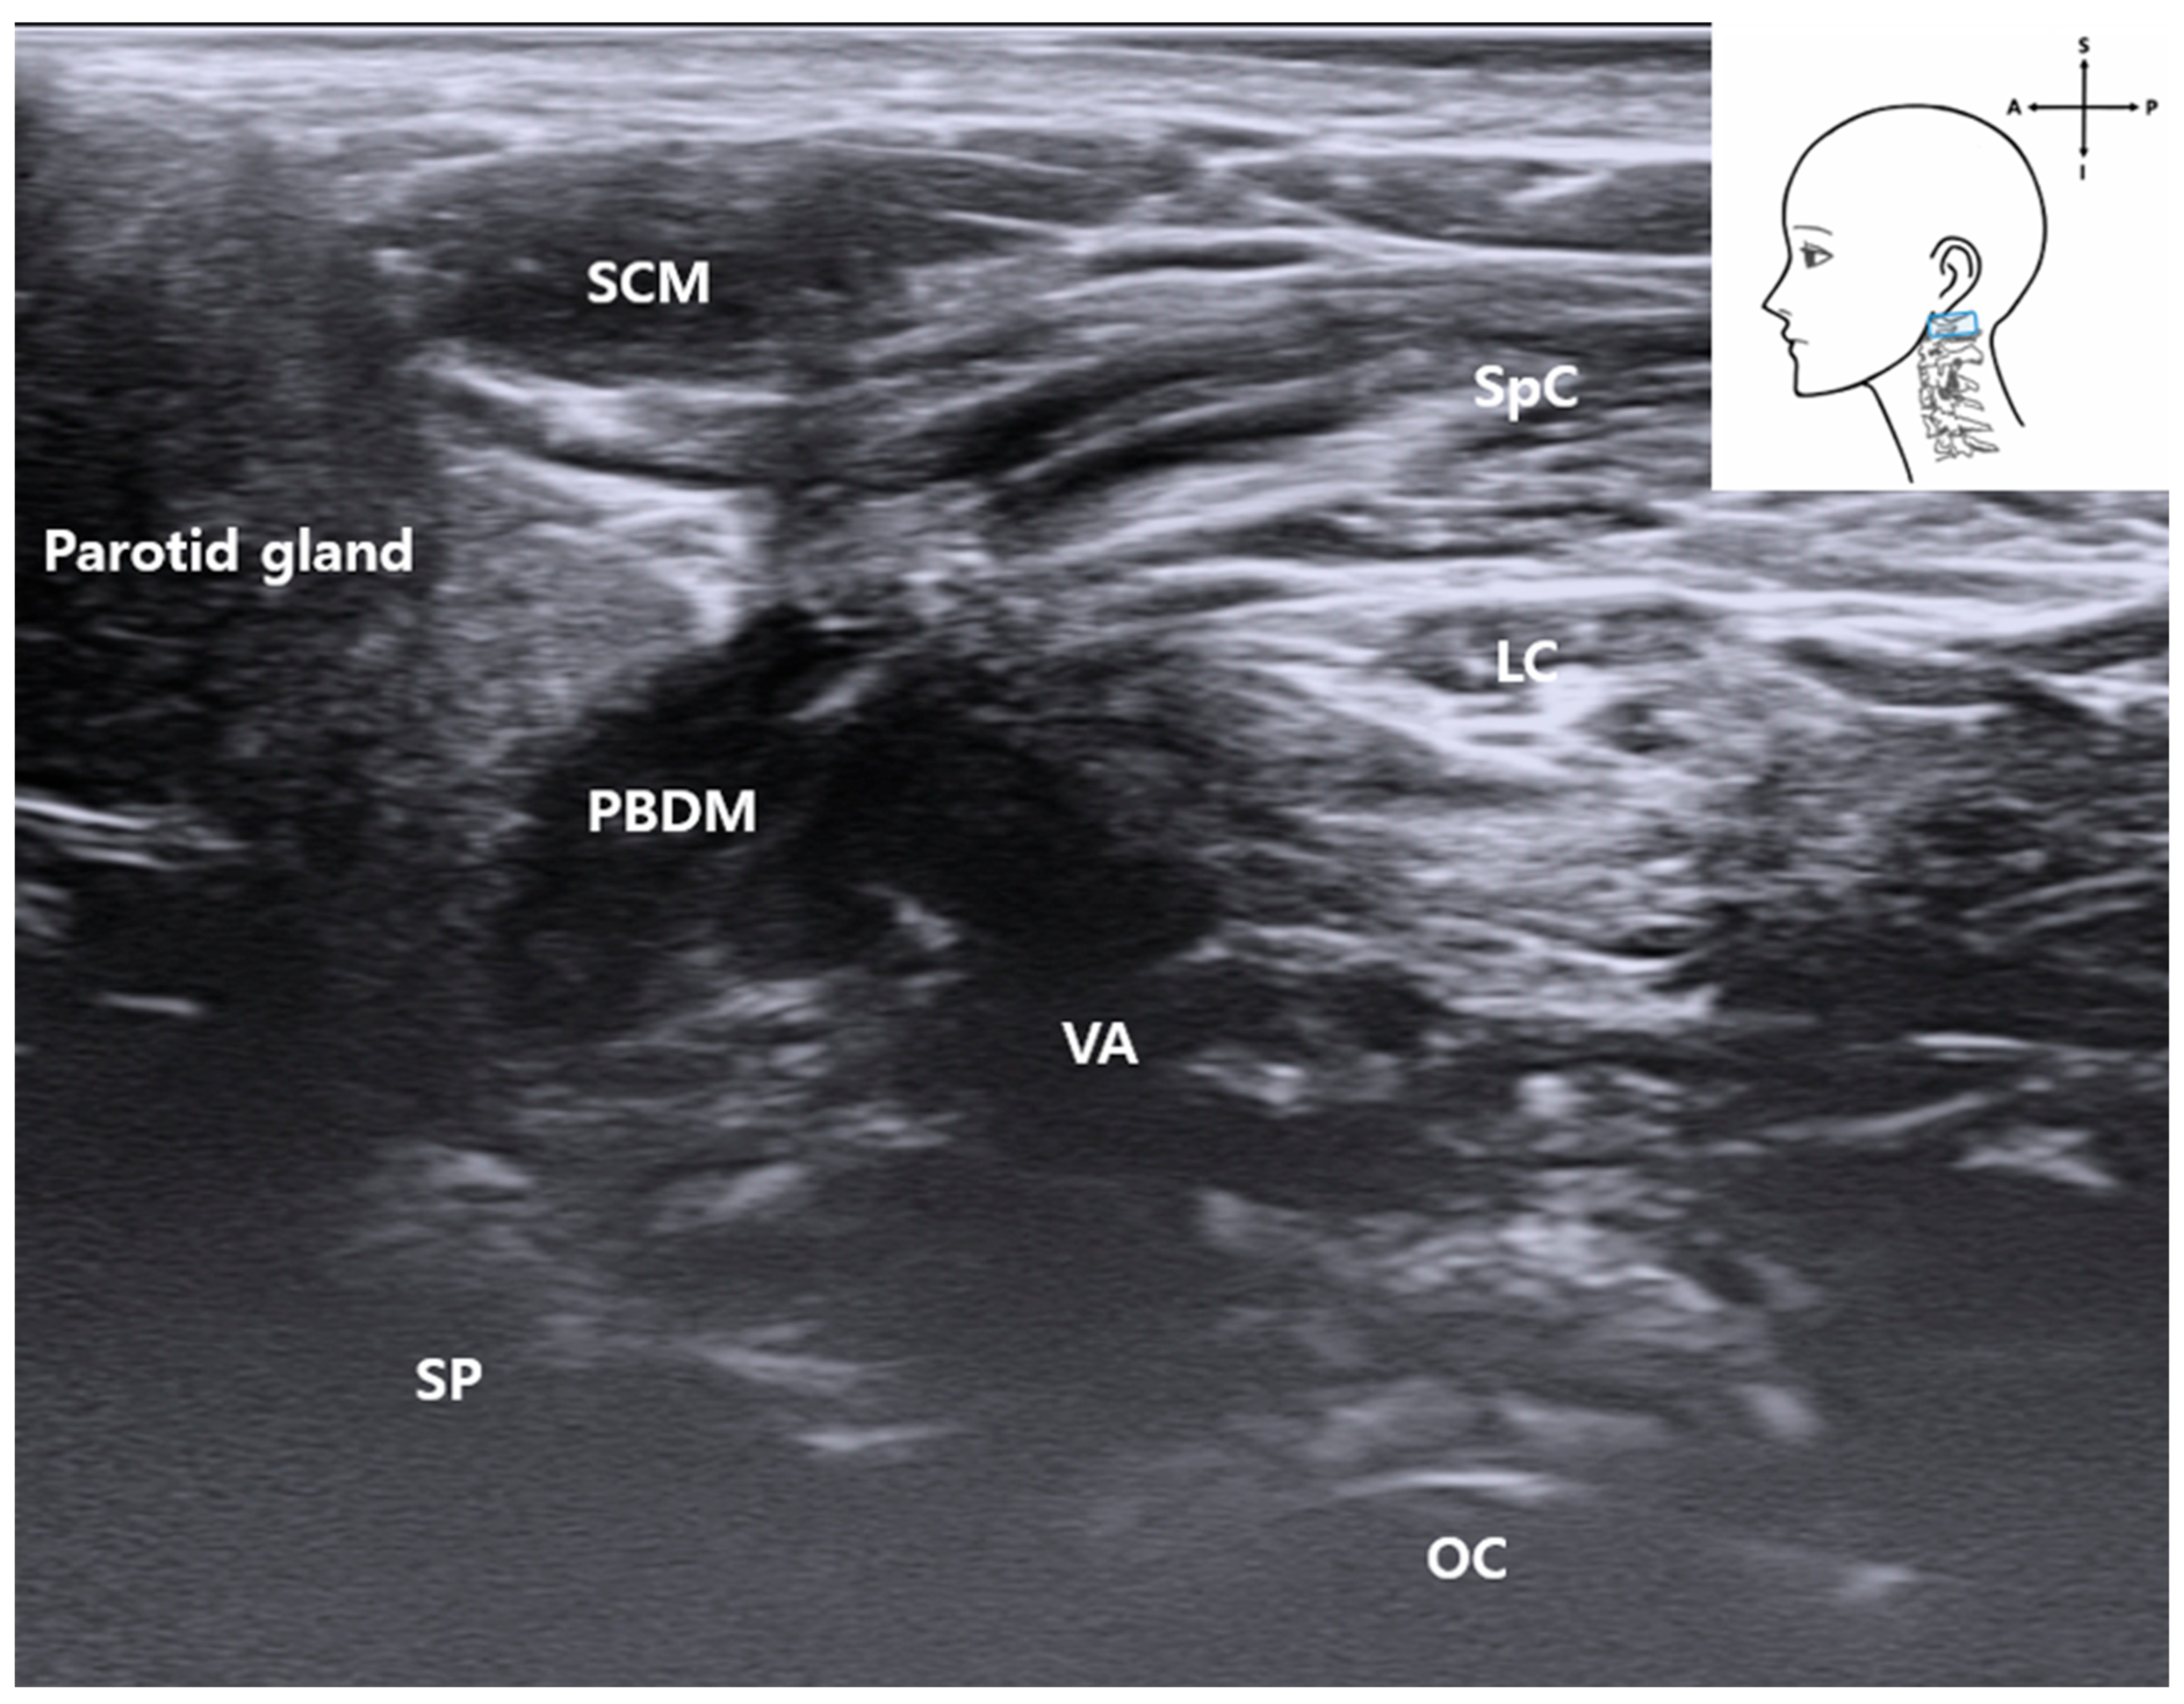

3.3. C1 Detection and Muscles

3.4. Identification of the Vertebral Artery (VA)